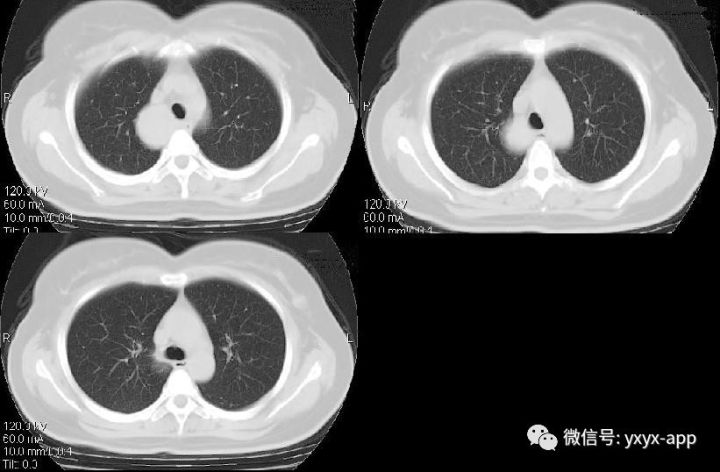

纵隔支气管囊肿1例CT影像表现

【基本资料】女,57岁

【主诉】胸疼、胸闷2月余

CT值在50-60hu之间

肚肚丫头:右上后纵隔、气管右旁、脊柱前方可见类圆形软组织密度影,与气管及食管均关系,增强后无明显强化,考虑囊肿,起源待定。